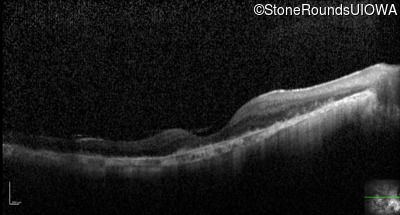

Optical Coherence Tomography - Left - 20/63 +2

Exemplar / OCT Stack

OCT Stack